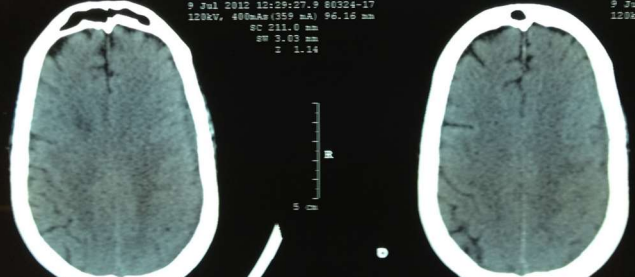

Fig 1,2,3,4,5,6,7,8,9,10,11,12,13,14,15

Figure 1

Figure 2